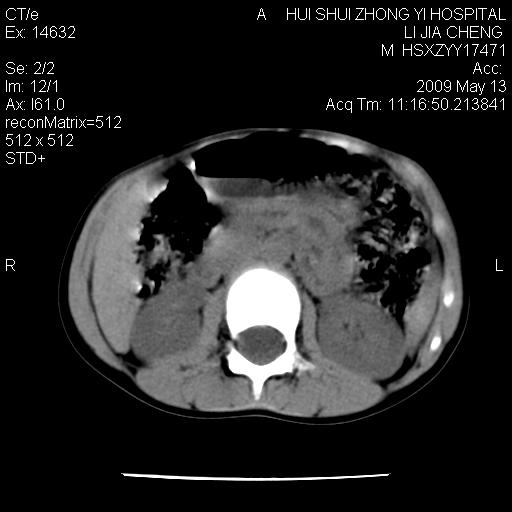

肠道准备不足,im15---------------------18左侧腹腔病变?

肠管管壁均匀增厚,炎性可能

考虑腹疝可能。

是小肠,壁稍厚可能是肠腔未很好充盈所致,腹部ct扫描未见明显异常。